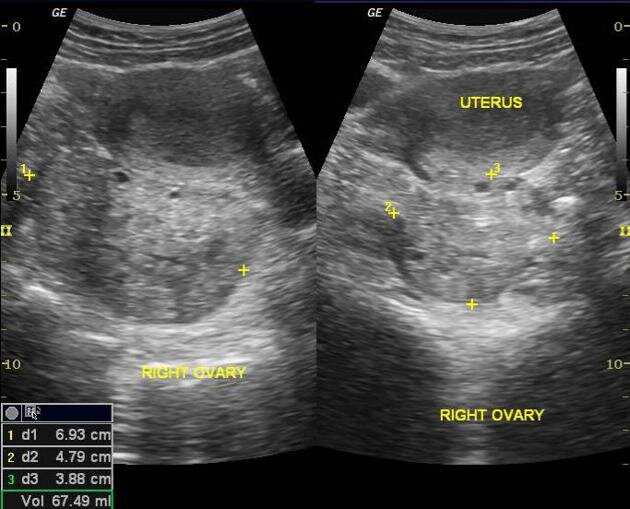

Enlarged ovary with peripheral follicles.

What is ovarian torsion?